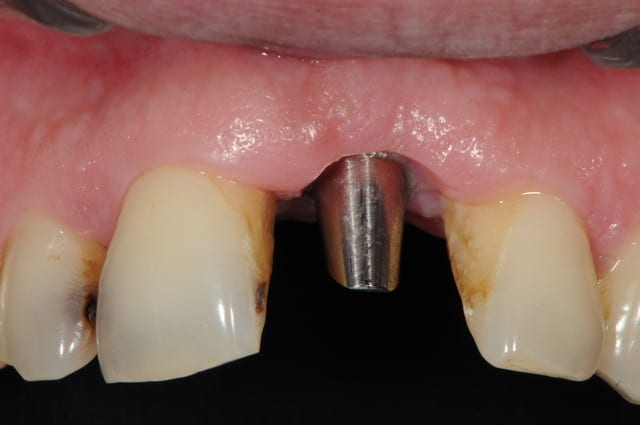

Un pilier de cicatrisation customisé ou personnalisé c'est une vis de ciatrisation individualisée : elle peut être faite de plusieurs facons par exemple à partir de ton porte implant que tu modifies par apport successif de composite.

Ca ressemble à cela :

sinon, tu peux toujours partir d'un pilier standard et tu fait une provisoire dessus qui s'adapte au mieux...

comme olivier tu en sacrifies une vingtaine, mais bon, c'est pas grave tu peux t'en re-servir.